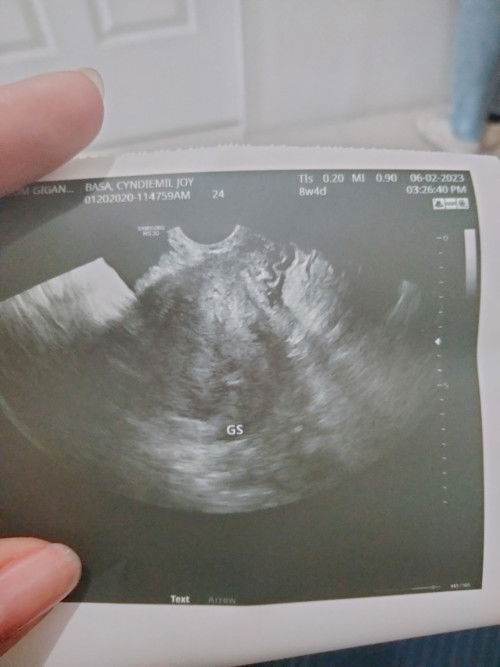

Last 2 weeks ago, nagpost din po ako dito mga mi. 2x nako nag pa tvs pero wala pading baby. Base sa lmp ko dapat 11 w and 4 days na ako today. Pero nagbalik ako sa ob ko nung june 2, and heres the update . NAG SHRINK NA DAW PO YUNG GEST SAC KO. NAGTATAKE NA DIN PO AKO NG MGA MEDS PAMPADUGO. PERO WALA PADIN PONG EFFECT SAKIN. WALA PARIN KAHIT NA ANONG PAIN AND EVEN BLEEDING. #advicepls #pleasehelp #bantusharing #FTM #respect_post #preganancyjourney

WALA NA PO BA TALAGANG CHANCE TO? UMAASA PA DIN PO AKO. LAST TWO WEEKS AGO NAGPA TVS AKO, AND 5WEEKS PALANG DAW AKO BASE SA ULTRASOUND, GESTATIONAL SAC PALANG AND WALA PANG BABY THEN SABI NG OB KO WAIT KAMI NG ANOTHER 2 WEEKS ULIT KUNG LILITAW SI BABY. THEN KAHAPON CHECK UP KO ULIT AND TVS WALANG BABY, WALANG EMBRYO. YUN PADIN YUNG SAC LANG YUNG ANDUN. PWEDENG BLIGHTED OVUM NA DAW AKO. WALA NA BA TALAGANG CHANCE TO😭😭 ##pleasehelp #advicepls